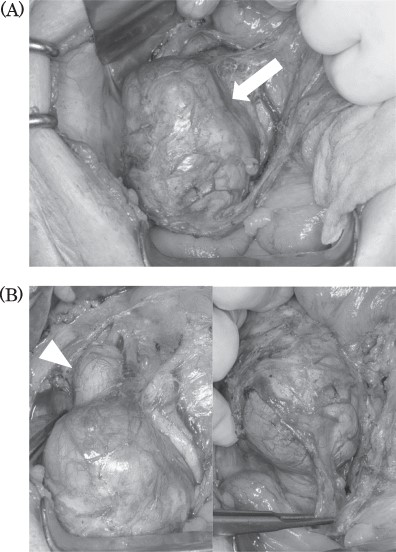

Intraoperative findings: tumor located in the retroperitoneum (A, arrow). Tumor did not invade to any other organs. Right ovarian vein throughout the tumor and tumor thrombosis was detected (B, arrowhead).

Intraoperatively, the tumor was located in the right retroperitoneal space and did neither adhere to nor invade other organs. The right ovarian vein ran cranially to caudally through the tumor. A central tumor thrombosis was detected in the ovarian vein (Fig. 5). We performed the resection of the tumor together with the right ovarian vein. The specimen showed a grayish-white solid tumor with the ovarian vein passing through its center (Fig. 6). Microscopically, fascicular hyperplasia of eosinophilic spindle cells with high-grade dysplasia and atypical mitotic figures were detected. Elastic fibers of the vessel wall were identified in the tumor. Immunostaining revealed that the tumor was positive for smooth muscle actin and desmin and negative for s-100 protein and c-kit. Based on these findings, our diagnosis was a LMS arising from the ovarian vein (Fig. 7). The immediate postoperative course was uneventful and the patient was discharged on day 11 postoperatively. Five months after the surgery, multiple lung metastases were detected on CT and chemotherapy was initiated (doxorubicin + olaratumab).